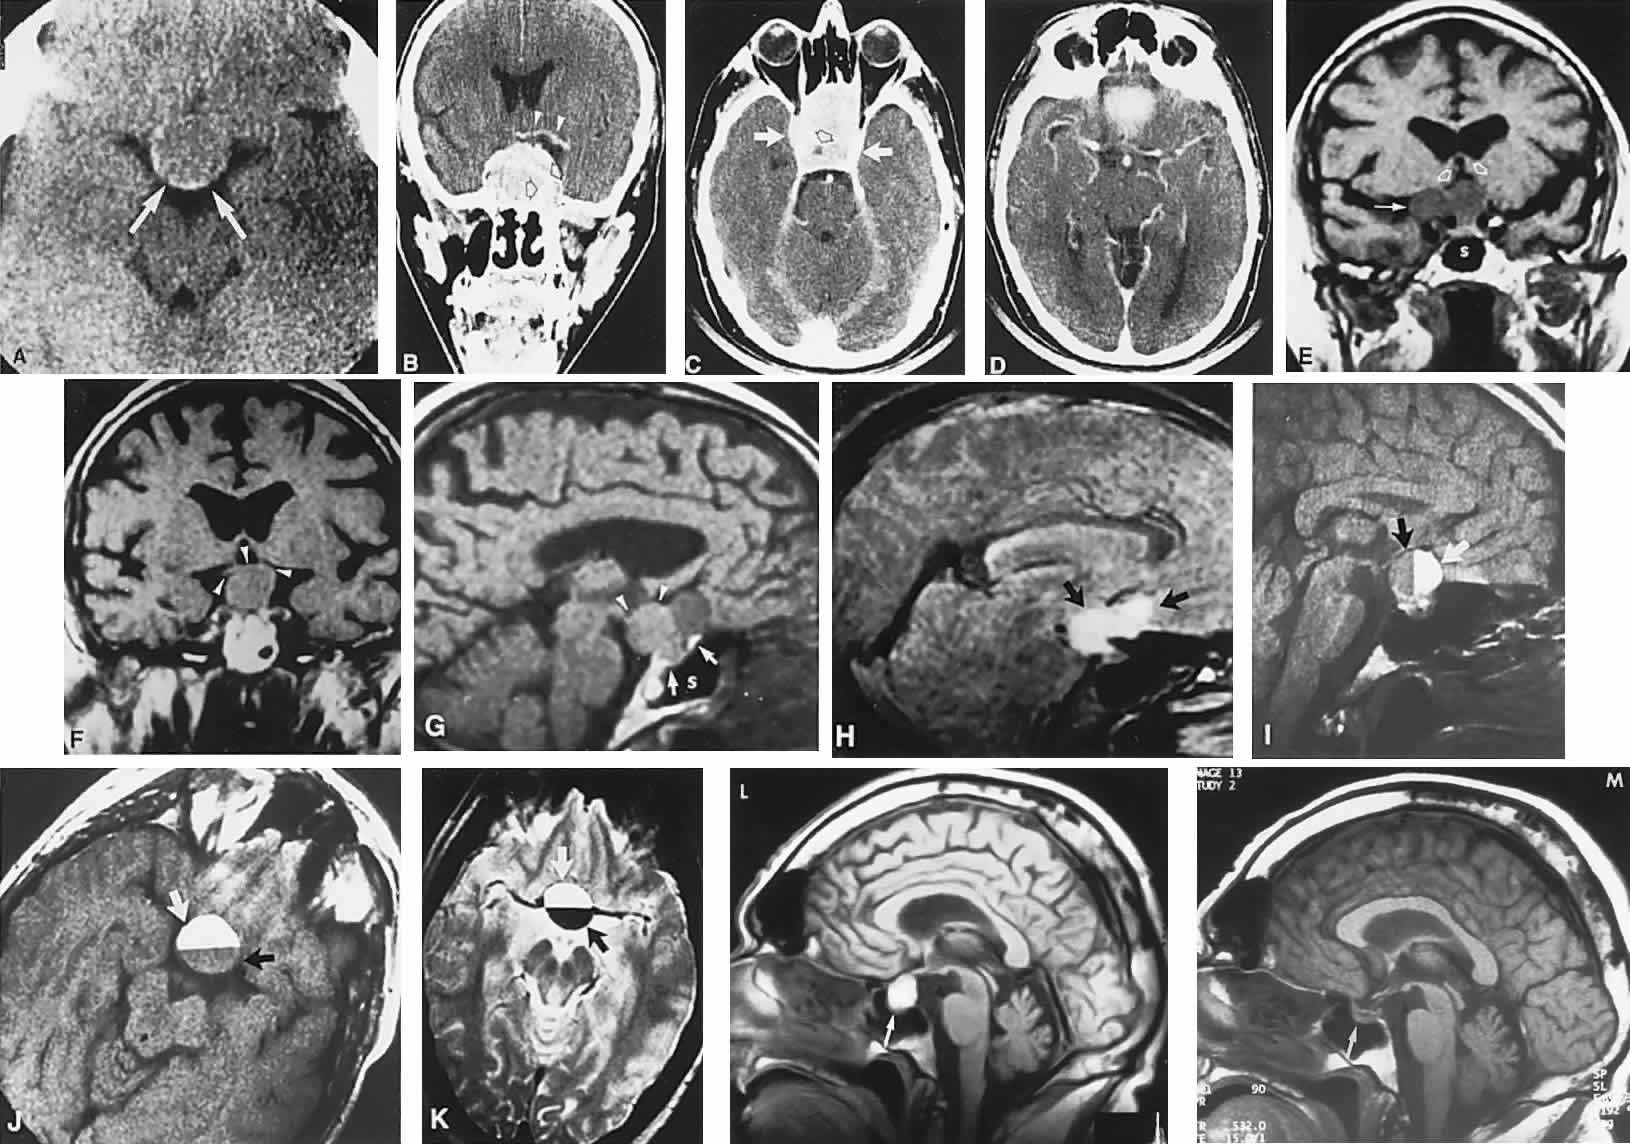

Clinical signs and symptoms include the following: acute onset of severe headache, often sickening frontal or retro-bulbar cephalgia, or other less disabling change in headache pattern; acute or rapidly progressing unilateral or bilateral (usually asymmetric) ophthalmoplegia due to rapid expansion into cavernous sinuses (see also Volume 2, Chapter 12); epistaxis or CSF rhinorrhea when the mass ruptures or erodes into the sphenoid sinus; complications of blood or necrosis debris in the CSF, with “pseudomeningitis”; rapid neurologic deterioration and obtundation, although patients need not be stuporous; and, greater or lesser degrees of hypopituitarism.62,63 Selective expansion laterally into the cavernous sinus may produce ophthalmoplegia without visual loss; selective expansion superiorly may produce visual loss without ophthalmoplegia. Almost without exception, enlargement of the sella is found even on plain skull film views; both CT and MRI detect fresh hemorrhage (Fig. 3), but MRI may fail to demonstrate acute hemorrhage unless specific sequences are employed (hemorrhage may be isointense on T1-weighted images and hypointense on T2-weighted images; in the subacute phase, extracellular methemoglobin should appear bright on both T1 and T2 sequences). Corticosteroid replacement and other supportive measures may be critical, and, in most instances, decompression through the sphenoid sinus is advisable, sooner rather than later. Bromocriptine has been suggested as a temporizing measure when signs and symptoms are modest and not progressing,64 and there are advocates65 for conservative management consisting of intravenous dexamethasone, so long as visual deficits are minimal or rapidly improve; otherwise decompressive surgery is required. Given the regularity with which pituitary apoplexy is often a delayed diagnosis, being confused with ruptured aneurysm or meningitis, for example, and that transsphenoidal surgery is a relatively simple undertaking, further procrastination in decompression of the compromised visual pathways is to be avoided.

Fig. 3. Neuroimaging of pituitary adenomas. A. Axial computed tomography (CT) section shows a round tumor mass filling the suprasellar cistern; ring enhancement (arrows) indicates subcapsular hemorrhage. B. Contrast-enhanced coronal CT section through a large invasive adenoma. Note encasement of the carotid artery (arrows) and the position of the middle cerebral artery above (arrowheads). C. Axial CT section shows lateral expansion into the cavernous sinuses (white arrows) and a necrotic cyst (black arrow). D. Subfrontal superior extent of the mass. Note the middle cerebral arteries. E. Magnetic resonance imaging of a large lobulated prolactinoma, with suprasellar extension. Note the distortion of the third ventricle (open arrows) and extension toward the temporal lobe (long arrow); the tumor has not involved the sphenoidal sinus (s). F. Chiasm (arrowheads) is draped on the superior surface of the tumor (TR, 550 milliseconds; TE, 26 milliseconds). G. Sagittal section shows suprasellar growth with the chiasm above (arrowheads); the sella (arrows) and sphenoidal sinus (s) are normal (TR, 850 milliseconds; TE, 26 milliseconds). H. Hyperintense signal (TR, 2000 milliseconds; TE, 60 milliseconds) indicates the partial cystic character. Sagittal (I) and axial (J) sections with head tilt to the right, in case of a large cystic adenoma with an interface level between newer blood (white arrow) and older blood (black arrow) (TR, 800 milliseconds; TE, 30 milliseconds). K. Signal difference is intensified (TR, 2100 milliseconds; TE, 80 milliseconds). L. Hemorrhage (bright signal, arrow) in a pituitary adenoma with headache and bitemporal field depressions. M. Without interventions, 2-month follow-up showed spontaneous involution, with normal pituitary gland (arrow), stalk, and chiasm.